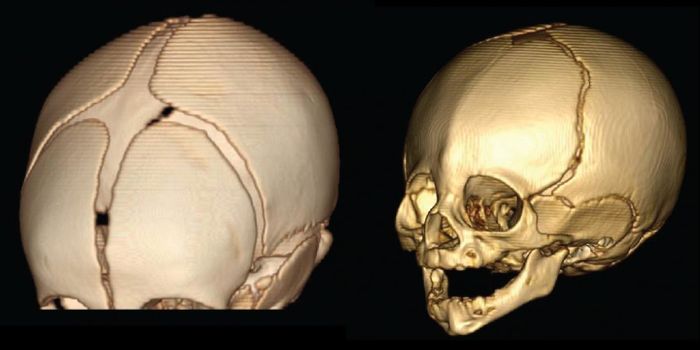

SEP 10, 2016Genetics & GenomicsWhen the bones of an infant’s skull fuse too early, the growing brain is dangerously confined to a small space, ca ...

MAR 11, 2016Clinical & Molecular DXHealth officials have long suspected a correlation between the Zika virus and microcephaly, but they didn’t know t ...